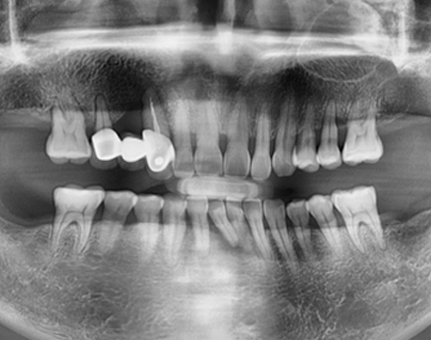

문치과 임플란트 사례

모든 전후 사진은 단순한 비교가 아닌,

환자분의 고민과 변화의 기록입니다.

문치과는 각자의 사연에 맞는 해답을 찾습니다.